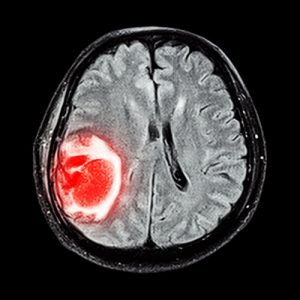

Внутримозговые опухоли – новообразования, которые могут иметь доброкачественную или злокачественную природу. Согласно медицинской статистике, на долю опухолей нервной системы (в частности, опухолей мозга) приходится 5% от всех новообразований.

Если изначально патология возникает в тканях мозга, то ее называют первичной опухолью. В случае, когда новообразование мозга является следствием метастатического процесса, то его называют вторичным. Это наиболее распространенная разновидность опухоли мозга, когда раковые клетки проникают в нервную систему из других органов.

В зависимости от степени идентичности (схожести) опухолевых клеток с нормальными клетками мозга, принято выделять 4 степени прогрессирования болезни:

- первая – клетки опухоли по внешнему виду сильно похожи на здоровые клетки мозга;

- вторая – опухолевые клетки имеют меньшую схожесть с нормальными клетками мозга;

- третья – клетки опухоли заметно отличаются от нормальных клеток мозга;

- четвертая – клетки опухоли полностью отличаются от здоровых клеток и имеют высокую скорость роста.